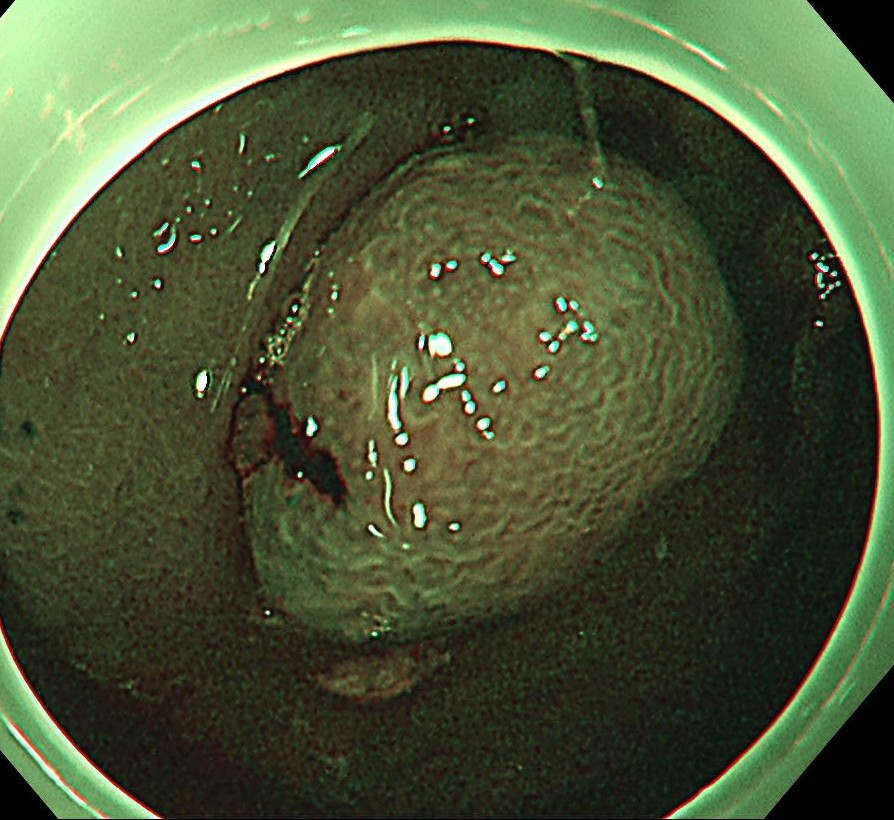

中年女性、下血にて来院。大腸内視鏡をしますと、直腸に15mm大のポリープを認めます。NBI(狭帯域光観察)では構造異形は乏しく、良性ポリープと診断しましたが、下血原因と考え、型のごとく内視鏡切除(EMR)しました。

病理診断にて直腸のSSA/P (sessile serrated adenoma/polyp 鋸歯状腺腫) と診断されました。大腸の鋸歯状腺腫はよくみられる病変ですが、右側結腸に多く、直腸は過形成性ポリープがほとんどで、直腸SSL (鋸歯状病変)は比較的まれです。またその多くが平坦な病変であるため、上記のようなⅠ型のポリープ形状は珍しい病変と思われます。最近の研究結果で直腸の隆起型のSSA/Pはがん化率が高いとする報告も散見され、注意を要する病変と思われます。